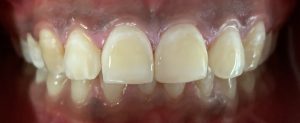

Department deals with all the treatments of teeth which alleviate pain due to pulp diseases and provide immediate solace to the patient. It also deals with the esthetic rehabilitation of the discolored, broken, mutilated teeth. Advanced endodontic treatment including micro-endodontics and regenerative therapy are also performed. Our department aims at creating and achieving excellence in the field of research and scientific development.

TREATMENTS

SERVICES